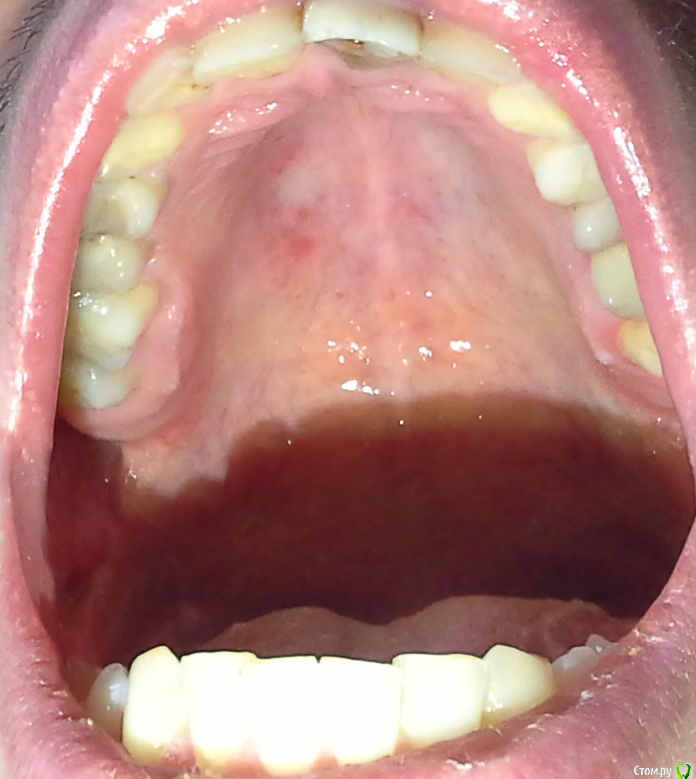

gekelbery Опубликовано 7 февраля, 2016 Поделиться Опубликовано 7 февраля, 2016 (изменено) Долгое время болит нёбо,на общем фоне выделяется белое пятно на слизистой, курю. Есть что-то подозрительное? http://s019.radikal.ru/i609/1602/60/ea6a70def04at.jpg Изменено 7 февраля, 2016 пользователем gekelbery Ссылка на комментарий

gekelbery Опубликовано 7 февраля, 2016 Автор Поделиться Опубликовано 7 февраля, 2016 около полугода Ссылка на комментарий

gekelbery Опубликовано 7 февраля, 2016 Автор Поделиться Опубликовано 7 февраля, 2016 (изменено) Rg есть?нету, нужно сделать какие-то обследования? Ко врачу не обращался, боль то появляется, то пропадает Изменено 7 февраля, 2016 пользователем gekelbery Ссылка на комментарий

red_butler Опубликовано 7 февраля, 2016 Поделиться Опубликовано 7 февраля, 2016 нету, нужно сделать какие-то обследования? Ко врачу не обращался, боль то появляется, то пропадаетА вот это зря, по интернету Вас все равно не вылечат. Сделайте ОПГ 2 Ссылка на комментарий